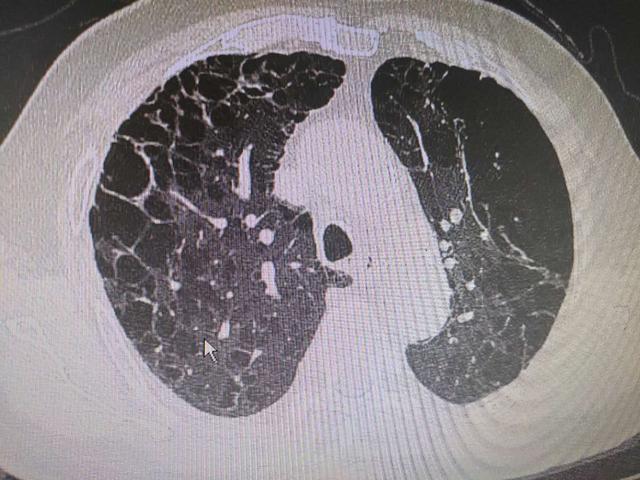

ct上满肺都是大泡泡,原因居然和这个有关|肺气肿|ct|慢阻肺|二氧化碳

图片尺寸640x480